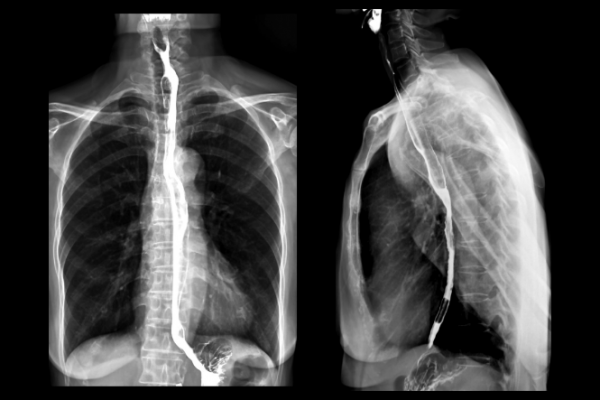

The image below is of a barium swallow.

X-ray image of a barium swallow in the oesophagus